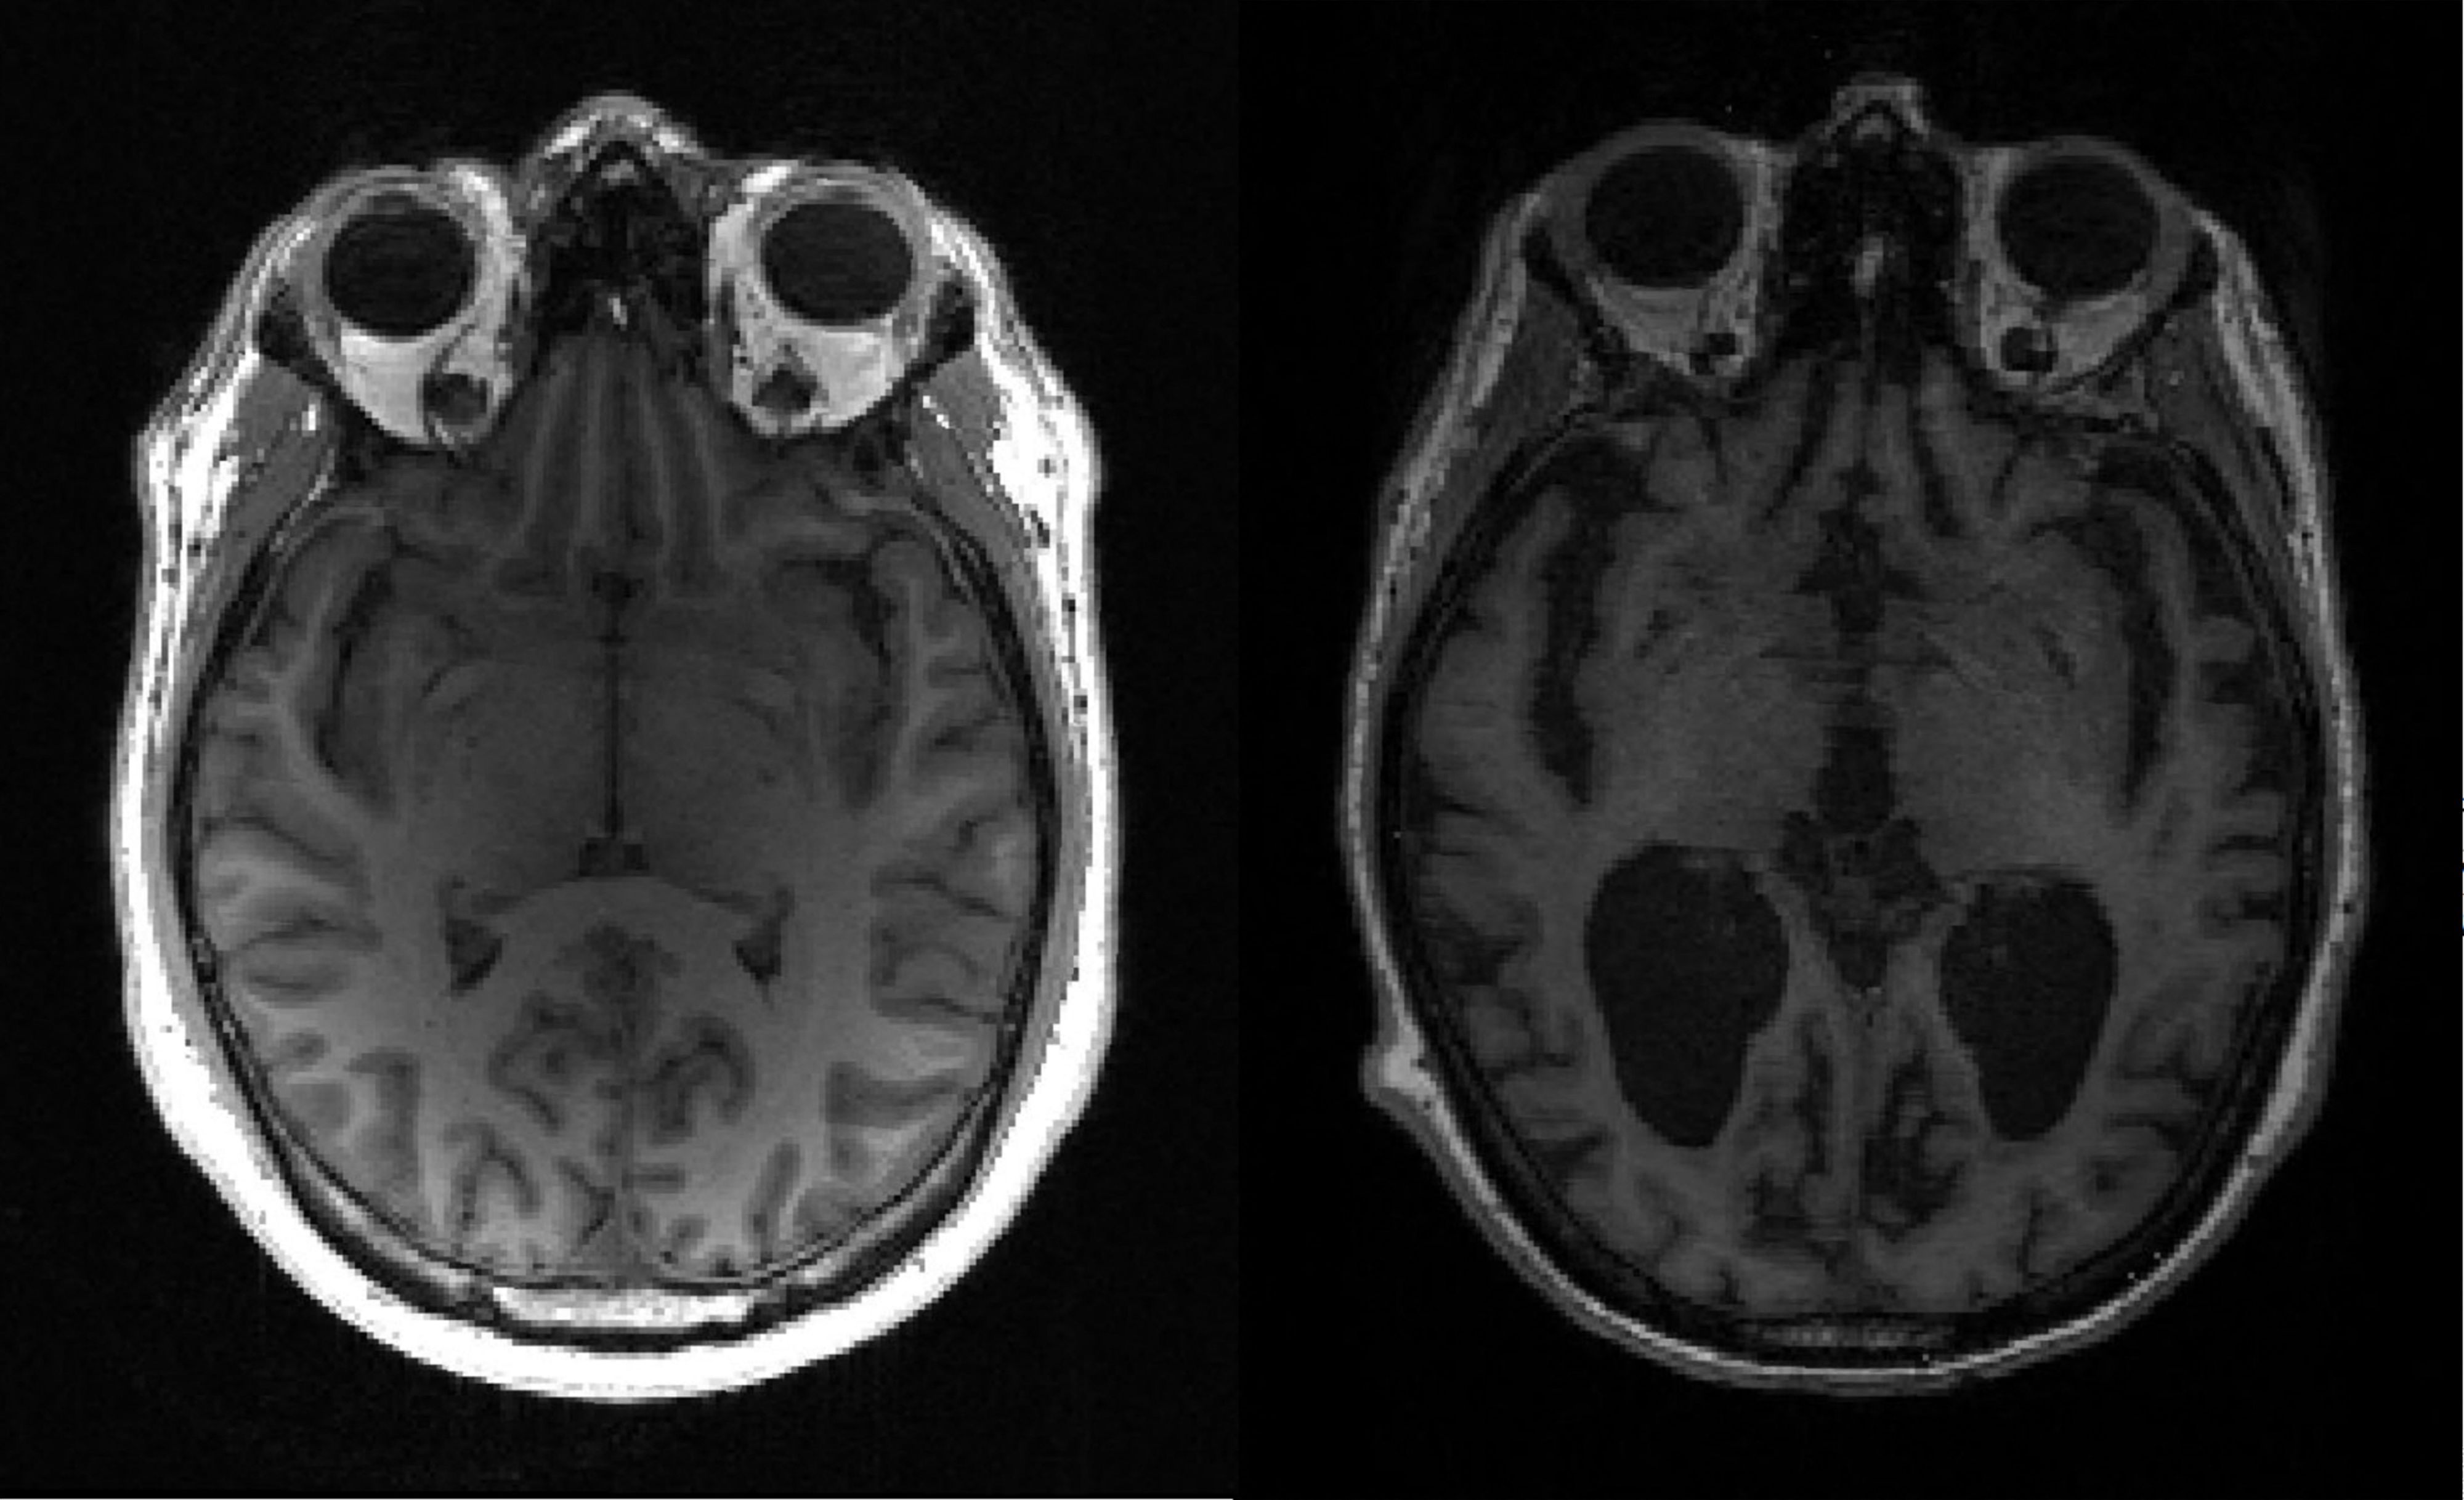

Penyakit Alzheimer sendiri didefinisikan sebagai gangguan neurodegeneratif yang irreversible dan progresif. Ciri umum dari penderita penyakit Alzheimer adalah penurunan kognisi dan memori, namun juga dapat terjadi perubahan perilaku, suasana hati yang sering berubah-ubah, gangguan bicara, menelan, bahkan gangguan berjalan.

Penyakit Alzheimer pertama kali ditemukan oleh Alois Alzheimer pada tahun 1906. Pada penderita penyakit Alzheimer dapat dilihat adanya pembentukan plak amiloid serta penumpukan protein (neurofibrillary tangles) pada sel saraf otak. Hal ini menyebabkan terganggunya komunikasi antara sel saraf otak yang satu dengan lainnya dan bahkan bisa menyebabkan kematian sel saraf otak. H

ingga saat ini belum diketahui secara pasti apakah penyebab dari penyakit Alzheimer’s ini namun diduga berhubungan erat dengan stress oksidatif serta inflamasi. Adapun, pengobatan yang ada saat ini adalah untuk memperlambat progesifitas dari penyakit ini, salah satunya dengan memberikan obat-obat penghambat enzim asetilkolinesterase.

Pada penderita penyakit Alzheimer diketahui adanya penurunan neurotranmiter asetilkolin, sehingga untuk mempertahankan jumlah asetilkolin yang cukup pada sel saraf otak, dilakukan penghambatan pada enzim asetilkolinesterase.